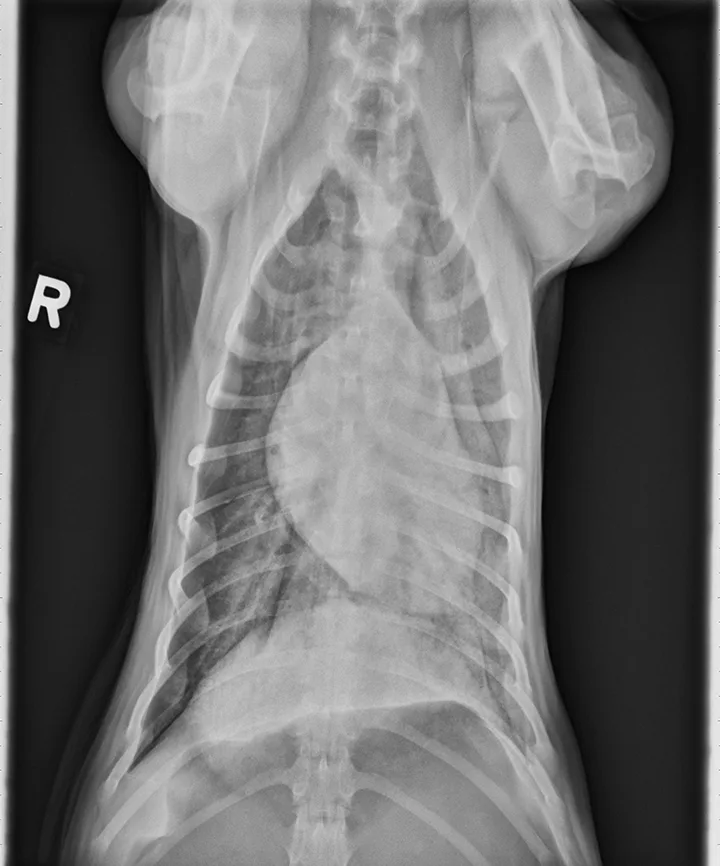

Lateral thoracic x-ray of a dog showing diffuse opacity of lung parenchyma.

Thoracic radiographs can appear normal initially, but changes to the pulmonary parenchyma may become more apparent within 24 to 72 hours as respiratory injury progresses. Evidence of patchy pulmonary edema with bronchial, interstitial, or alveolar patterns may be observed [Figures 1 and 2].6,13,16,19 Right middle lung lobe consolidation and pleural effusion in cats have been reported.6,13,16 An alveolar pattern may be seen on serial radiographs in patients that develop secondary bacterial pneumonia.6

FIGURE 1

A severe, diffuse patchy interstitial-to-alveolar pattern, more severe in the mid-to-caudodorsal lung fields, in a dog with smoke inhalation injury after a house fire